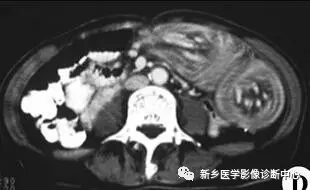

13 肠梗阻

文章图片

1.肠梗阻:中腹部多发阶梯状 , 马蹄状液平 。 2.空肠不全性梗阻 。

1.空肠不全性梗阻:空肠扩展呈弹簧状 。 2.空肠机械性梗阻:弹簧征